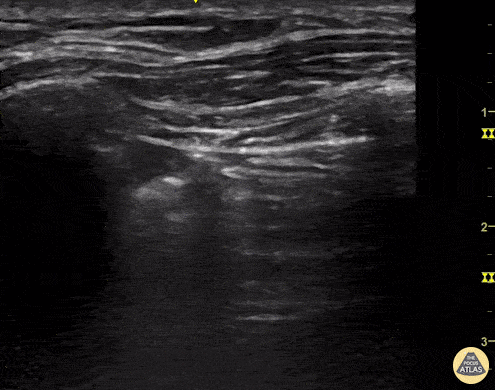

![]()

distance maximale entre la plèvre pariétale et la plèvre viscérale.